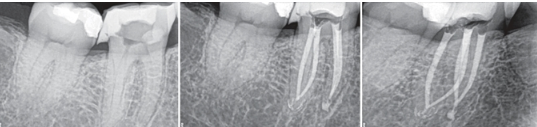

MTA 사용 전, 후 / 출처 : 치과신문

신경이 살짝 보였던 부위는 MTA라는 생체 친화적 재료로 보호막을 만들어주고 그 위를 강한 접착력을 가진 레진으로 복원하기로 했어요.

이 과정을 레진 빌드업이라고 해요. 단순히 구멍을 막는 게 아니라, 치아 본래의 힘과 모양을 되살리는 과정이죠^^

신경이 뚫린다고 해서 모두 다 신경치료해야 하는 것은 아니며 신경관의 복잡성 때문에 신경치료는 현대적인 관점에서 치료가 잘 되었는지 정확하게 파악할 수 없기 때문에 치과의사의 눈에 보이는 영역에서 마무리하는 것이 더 좋다는 생각이에요.

그래서 이분도 MTA라는 재료와 레진 빌드업 과정을 통해 치아를 지켜드리기로 한 거죠^^